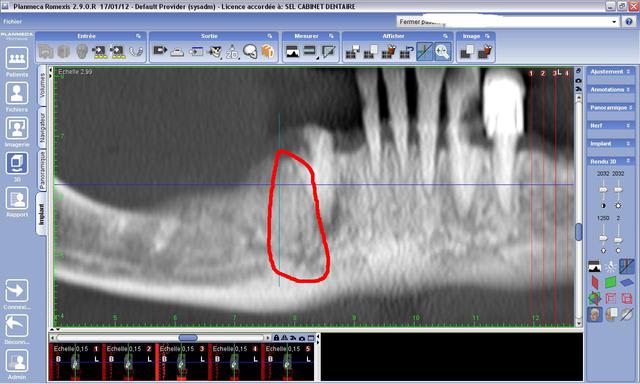

Pensez vous que cette continuité du nerf sera genant pour la pose d'un implant (trait violet) en terme de forage (je ne pense pas ), mais surtout en terme de sensibilité post-op

c'est pas le pedicule incisif qui inquiete docj, mais cette image qui ressemble à une branche du ndi et qui remonterait parralellement a la canine.

Le canal incisif mandibulaire va du trou mentonnier à l' apex de l' incisive centrale. Il contient le pédicule incisif.

Mais là, c' est en distal de la canine. C' est quoi?

le trou mentonnier, c'est entre la 4 et la 5, pas étonnant de trouver le canal incisif en distal de la canine...

Oui, mais en vertical, en distal de la canine, qui remonte?C' est pas le canal incisif qui se serait trompé de route!

Oui effectivement. Je parle de ce qui remonte en vertical en arrière de la canine. Merci

"En ce qui concerne ta question initiale, je ne peux pas vraiment te dire ce qu'il ce passera si tu touches ce rameau nerveux, ou même si tu le frôles juste. Par contre , il me semble réalisable de positionner l'implant de sorte de rester a distance du problème, tel que je l'ai dessiné sur ton image fourni en pièce jointe. il va de soi que, n'ayant pas de plan de traitement, je ne peux qu'estimer la position de l'implant en 44."